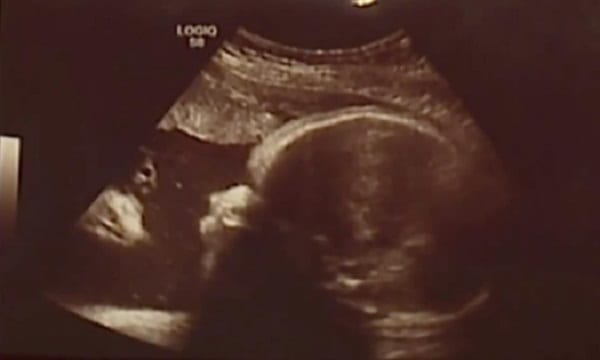

Elle a déclaré que l’échographie leur a donné une assurance après des complications lors de deux autres grossesses.

Leurs premiers enfants, un garçon et une fille, étaient tous deux nés avec des anomalies congénitales.

Leur première fille a une polydactylie pré-axiale – elle avait deux pouces d’une part – et le deuxième enfant est né avec un palais fendu, ont-ils dit à Fox 43.

Pour Zachary Smith, le père, bien que la famille ne soit pas particulièrement religieuse, elle a vu l’image comme un signe divin.

« L’ange ou Jésus, comme vous pouvez l’appeler, je le considère comme une bénédiction », a déclaré M. Smith.

« Quand je l’ai vu, ça m’a presque fait couler des larmes. J’étais sans voix, je ne pouvais pas y croire. »

Le couple a posté la photo sur Facebook, demandant aux gens de dire ce qu’ils voyaient dans l’échographie.

Bébé Briella est née le mercredi. La mère et la fille sont en bonne santé et se portent bien.